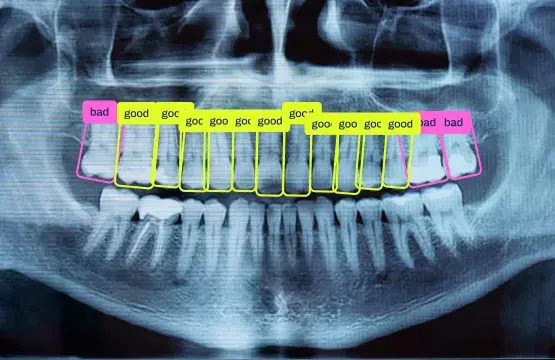

- 🩺 Healthcare: Assisting doctors by analyzing scans and flagging irregularities.